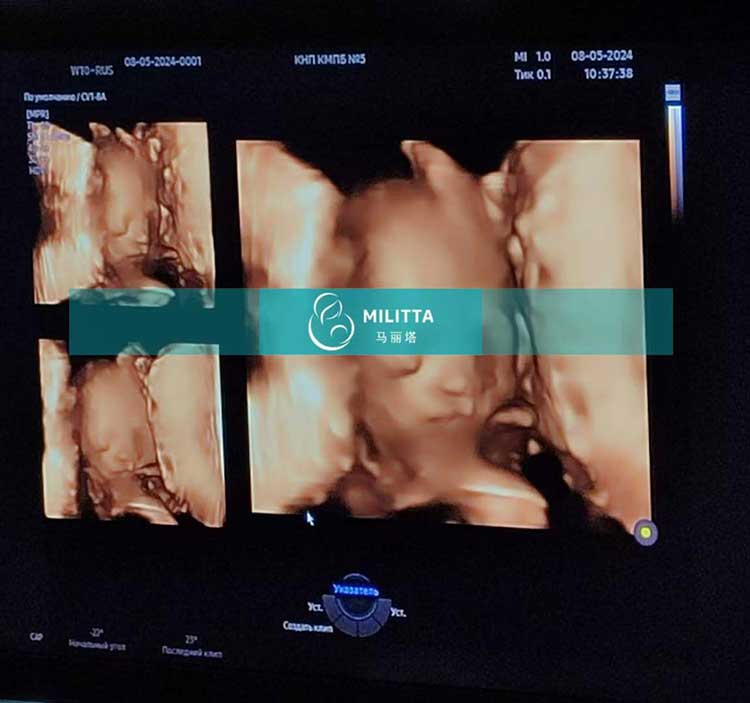

两位格鲁吉亚客户的乌克兰试管妈妈孕24周四维彩超检查

安排两位格鲁吉亚客户的乌克兰试管妈妈在基辅准时去做孕24周的四维彩超检查,胎宝宝各项身体数据都发育达标了,非常健康